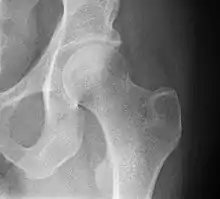

X-ray of the hip, with measurements used in X-ray of hip dysplasia in adults.[34]